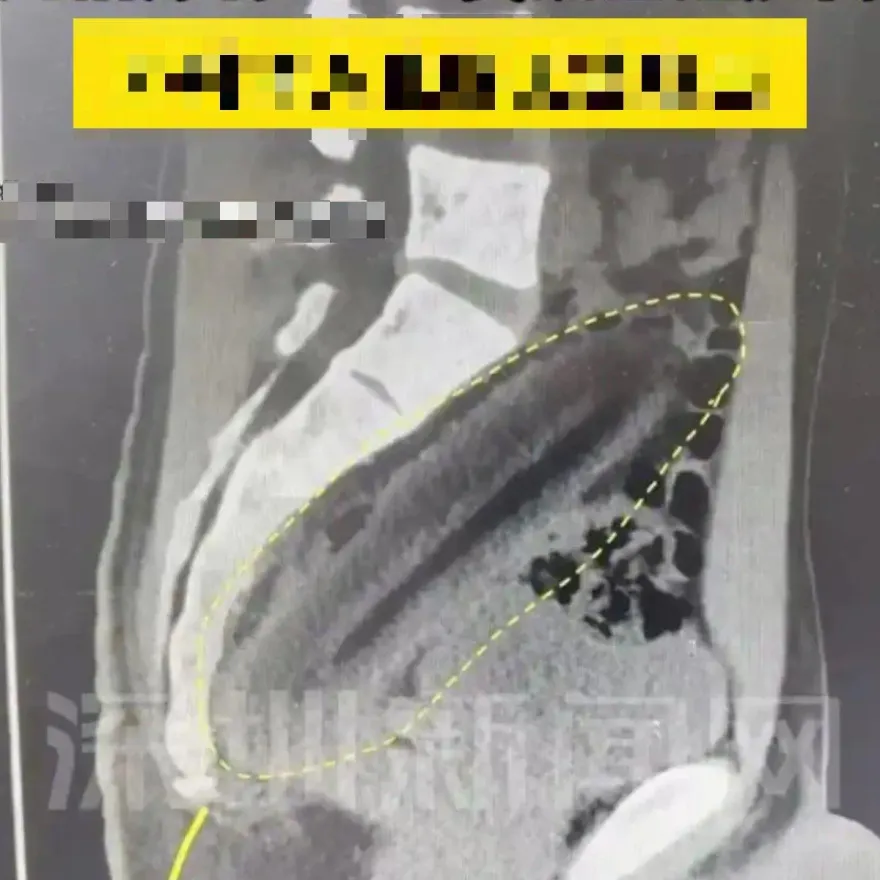

襪子

肺部

真菌

咳嗽